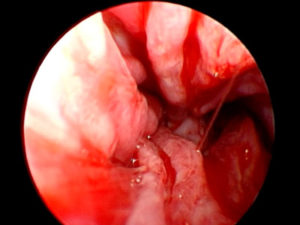

Endoscopia delle vie aeree

Con l’ endoscopia possiamo visualizzare le vie aree superiori dal naso ai bronchi e se necessario raccogliere campioni di liquido, cellule e tessuti da analizzare in laboratorio, permette anche di identificare e asportare corpi estranei. Viene eseguito da un medico specializzato con il paziente in anestesia e si rende necessario per la diagnosi di patologie croniche delle alte e basse vie respiratorie e in presenza dei corpi estranei.

Rinoscopia

Endoscopia del naso del cane.

A sinistra in uno stato patologico a destra in stato fisiologico